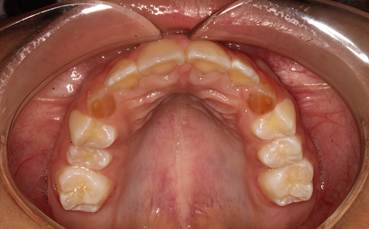

Figura 18. Vista del arco superior.

Podemos apreciar un arco superior en forma de U, paladar profundo, con una alineación dental adecuada. Piezas #53 y 63 con hallazgos clínicos de amelogénesis imperfecta.